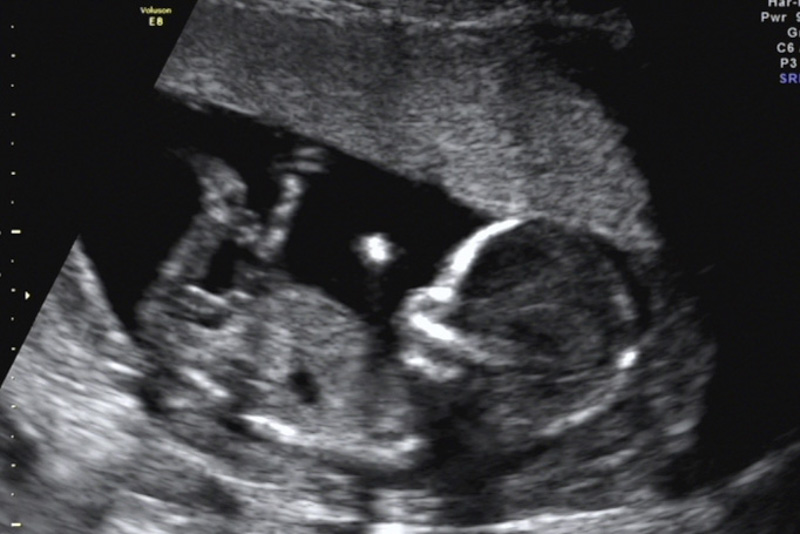

今年1月,石女士驚喜地發(fā)現(xiàn)自己懷孕了,然而在之后的孕檢過程中,檢查發(fā)現(xiàn)右附件區(qū)有一大小125mm×115mm×79mm囊性占位,混合回聲,考慮右側(cè)卵巢成熟畸胎瘤。由于囊腫巨大,內(nèi)部回聲雜亂,隨著孕期的增加,囊腫有可能發(fā)生扭轉(zhuǎn),導(dǎo)致破裂引起急性腹痛威脅母嬰安全。同時,巨大的腹腔占位可能影響子宮增大,限制胎兒的生長……

在大家的共同努力下,患者長在卵巢上的腫瘤被完整剝除,腹腔干凈,對子宮沒有騷擾,卵巢恢復(fù)正常大小,臍部術(shù)口自然成形,不留瘢痕,監(jiān)測胎心正常,手術(shù)順利結(jié)束!